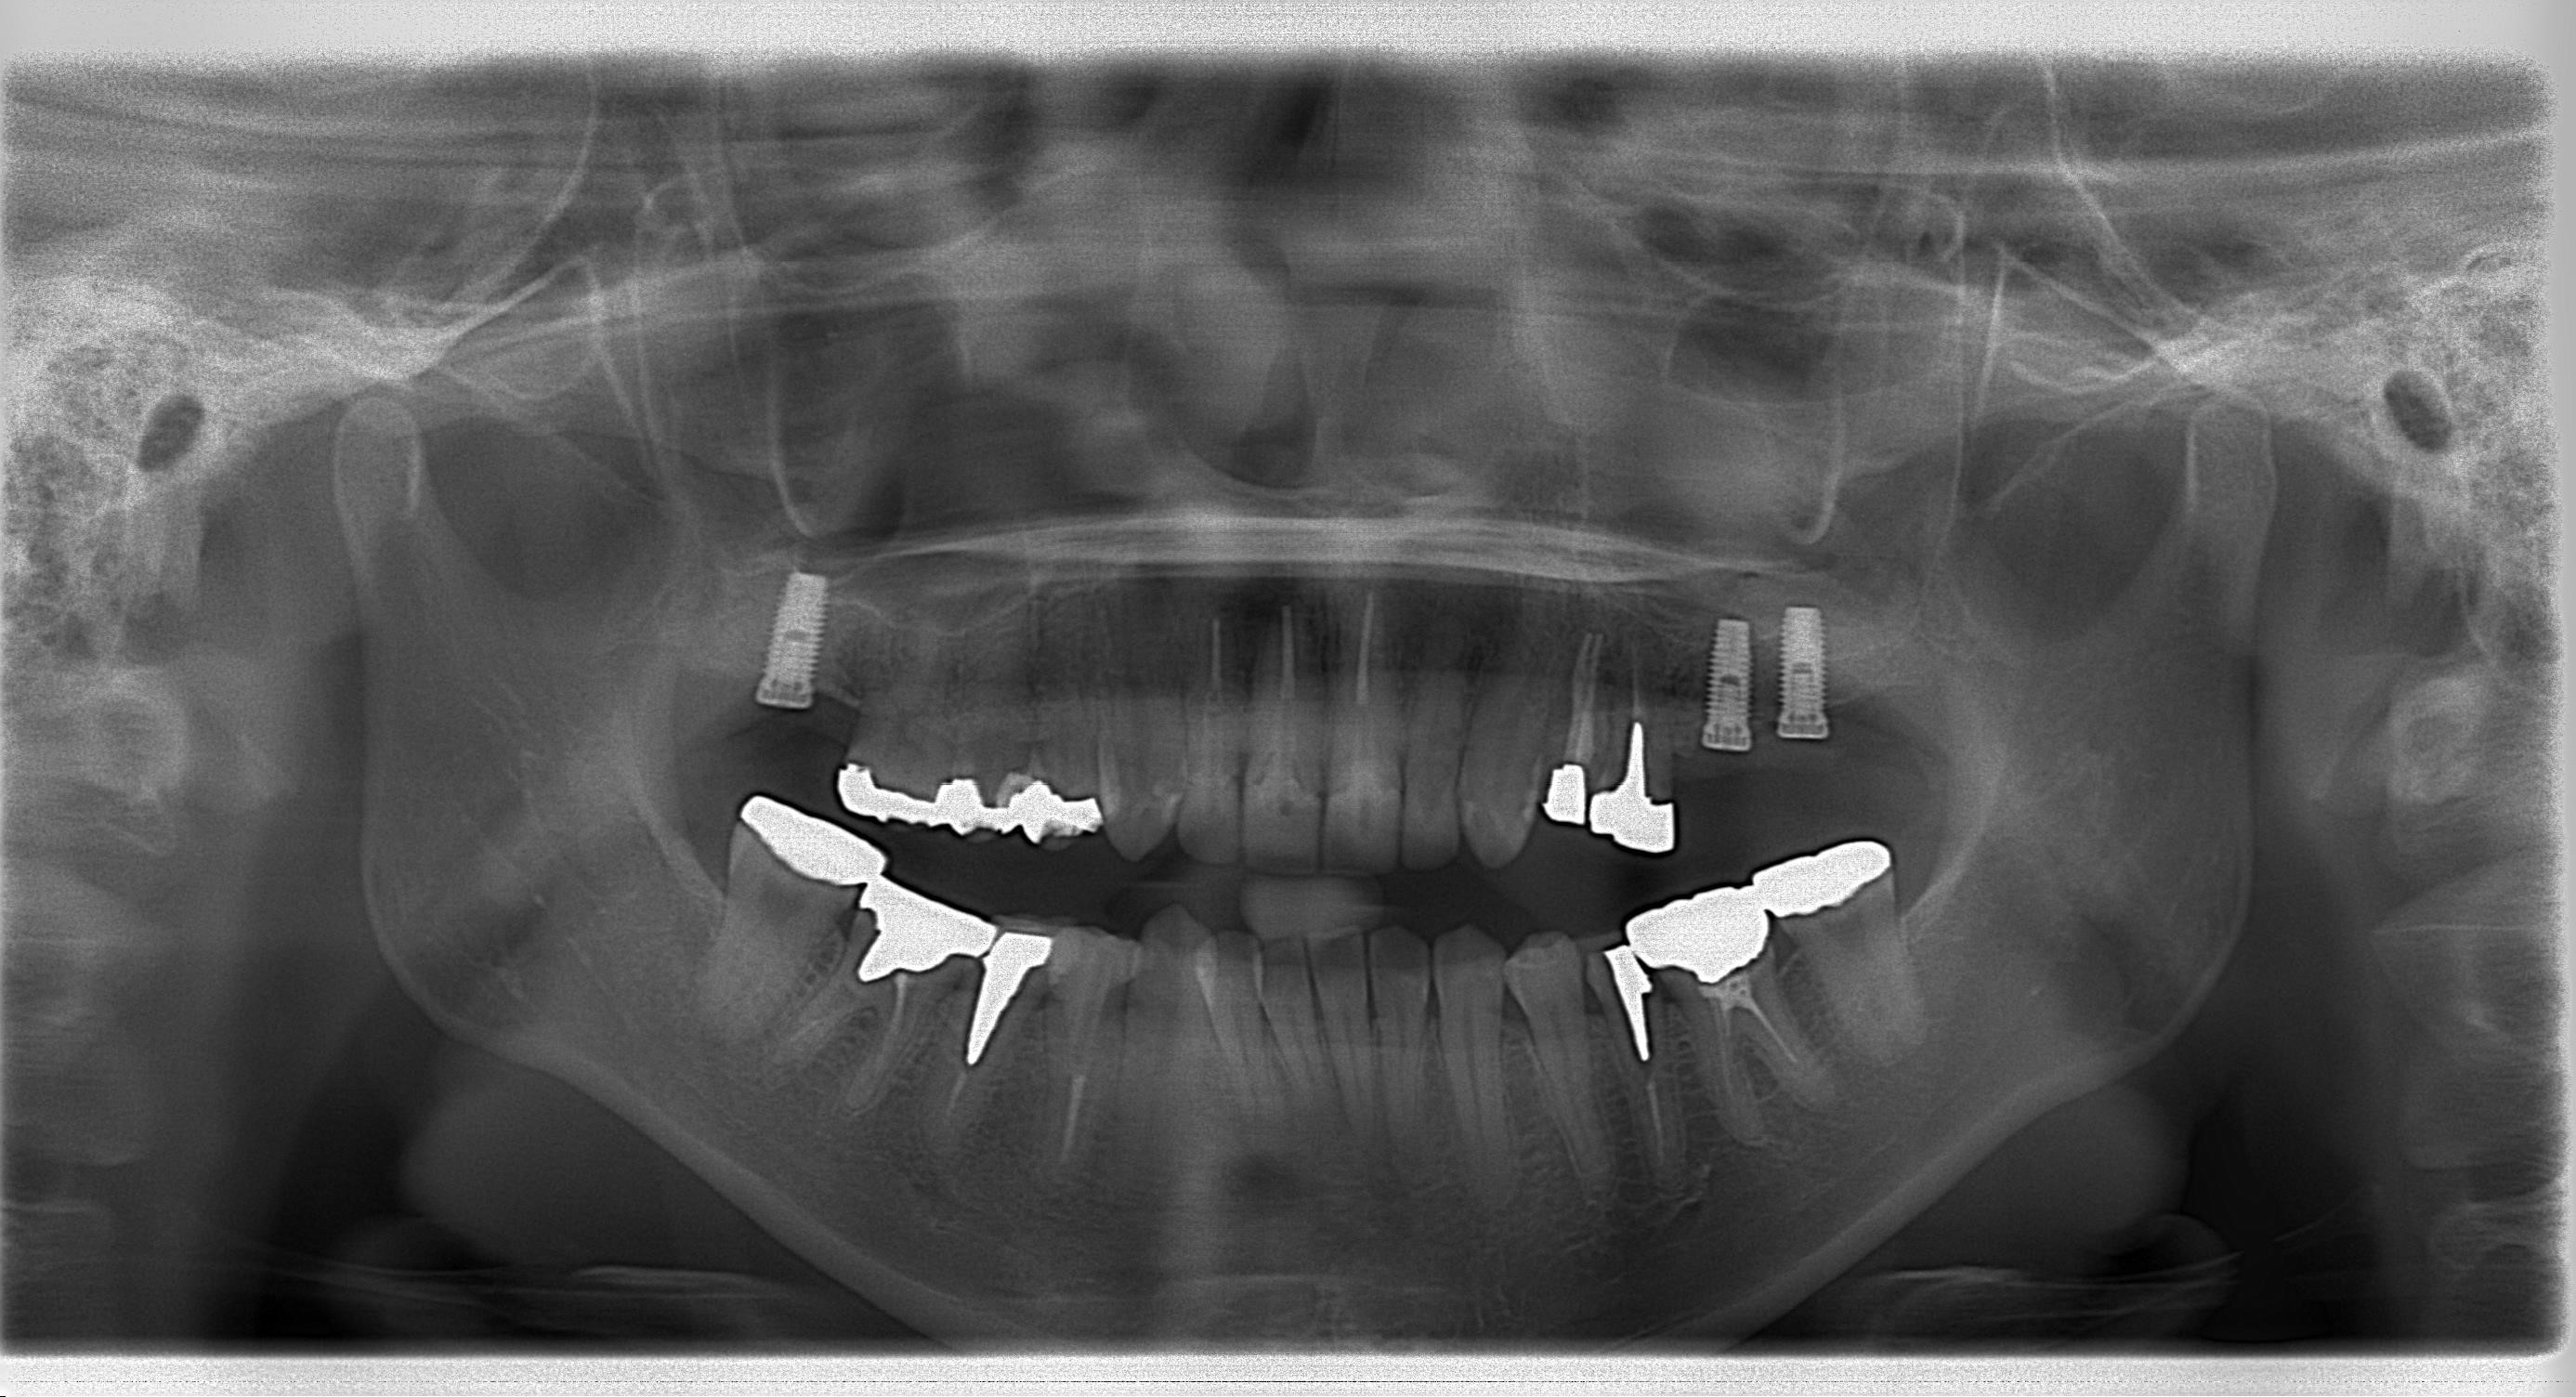

↓パノラマ

https://www.s-shika-clinic.com/asset/sainasu.jpg

2ケース目は

右下のインプラントを2本埋入いたしました。